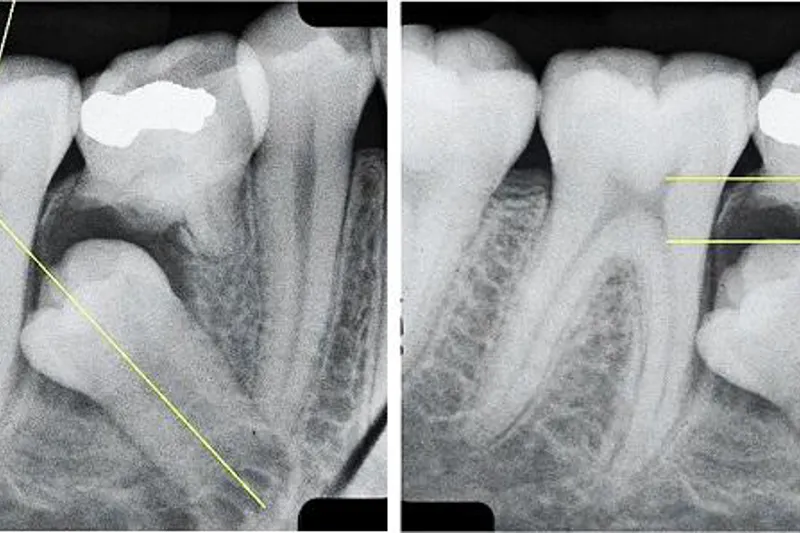

På basis af tændernes retentionsdybde og hældning i forhold til nabotandens længdeakse angav forfatterne følgende behandlingsmuligheder: ekstraktion af primær tand (dybde < 5 mm; hældning < 55°), kirurgisk blotlæggelse af permanent tandanlæg (dybde < 5,5 mm; hældning < 95°) og kirurgisk opretning af permanent tand (dybde >5,5 mm, uafhængigt af hældning).